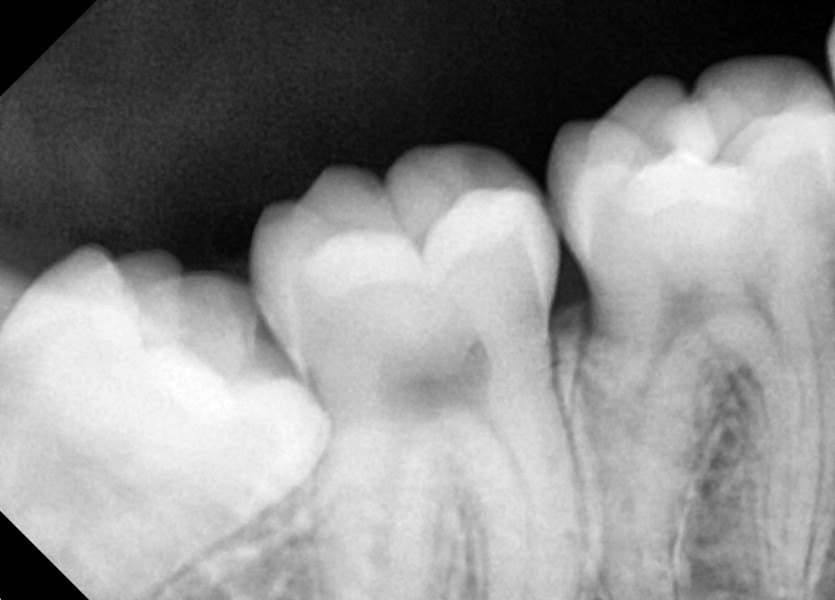

#18,28,38,48 사랑니 발치

구강 외과 전문의가 당일 발치했습니다.